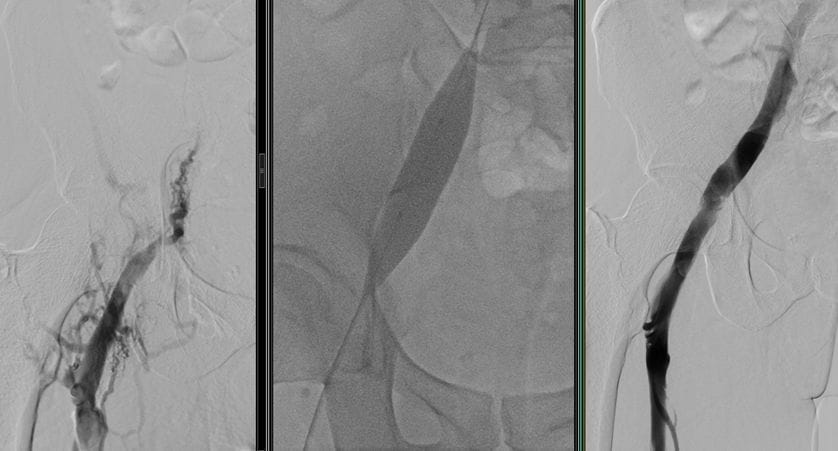

Behandlung von Gefäßverengungen durch Angiographie

Öffnung der venösen Gefäßverengung

In der modernen Medizin ist die Angiographie eine der effektivsten Lösungen zur Behandlung von Gefäßverengungen. Dank dieser Methode kann die Behandlung ohne chirurgischen Eingriff erfolgen und der Patient kann in der Regel noch am selben Tag entlassen werden.

Der Behandlungsprozess variiert je nach Größe und Lage der Verengung im Gefäß. Bei einer Verengung ist der Eingriff in der Regel einfacher und schneller. Bei einer vollständigen Verstopfung kann der Eingriff jedoch schwieriger werden. Zu den Hauptinstrumenten, die bei der Angiographie zur Behandlung von Gefäßverengungen verwendet werden, gehören:

• Atherektomie (Gefäßrasur)

Diese Eingriffe ermöglichen es, das Gefäß wieder zu öffnen und den Blutfluss zu normalisieren. Nach der Behandlung wird insbesondere bei Patienten mit Beinproblemen beobachtet, dass die Schmerzen beim Gehen erheblich reduziert oder vollständig beseitigt werden.